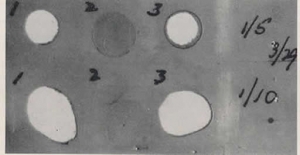

Fig. 17. A photograph in the paper (figure) shows gelatin film acted upon by stool suspensions from three individuals (1, 2 and 3). Concentrations of 1/5 on upper row and 1/10 are on the lower row being the more dilute.

In this paper previous work on stool trypsin was reviewed, even as far back as the first duodenal catheterisation by Hess AF (Am J Dis Child 1912; 4:205). Faecal suspensions were placed upon unexposed and unfixed gelatin film and the extent of removal (digestion) of the gelatin film noted. The gelatin was digested by the trypsin in the stool in more than 95% of non-CF infants whereas 209 of 220 (95%) of stool specimens from untreated infants with CF showed no tryptic activity whereas less than 5% of 500 controls lacked tryptic activity. Three separate stool specimens were recommended for diagnosis.

The photograph in the paper (Fig.17) shows gelatin film acted upon by stool suspensions from three individuals (1, 2 and 3). Concentrations of 1/5 on upper row and 1/10 are on the lower row being the more dilute.

1- Normal infant’s stool with extensive white areas where there has been extensive digestion of the gelatin by the trypsin in the stool.

2- Infant with cystic fibrosis – no digestion of gelatin.

3- CF infant on treatment with pancreatin now digesting gelatin.